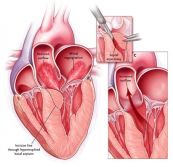

Dưới đây là hình ảnh mặt cắt cạnh ức trái cao trong siêu âm tim bẩm sinh. Mời các bạn tham khảo.

Dưới đây là hình ảnh mặt cắt trên hõm ức trục dài dọc động mạch chủ (Ao) trong siêu âm tim bẩm sinh. Mời các bạn tham khảo!

Dưới đây là hình ảnh mặt cắt trên hõm ức trục ngắn trong siêu âm tim bẩm sinh. Mời các bạn tham khảo!

Siêu âm tim là phương pháp chẩn đoán hình ảnh không xâm lấn, an toàn và được sử dụng rất phổ biến trong xác định những bất thường của tim. Dưới đây là hình ảnh mặt cắt quét cạnh ức trái trục ngắn trong siêu âm tim bẩm sinh. Mời các bạn tham khảo!

Tiến hành thăm dò các vị trí mặt cắt cạnh ức giúp đánh giá thất trái, so sánh kích thước các buồng tim và định khu tràn dịch màng tim, phân biệt tràn dịch màng tim và tràn dịch màng phổi. Dưới đây là hình ảnh mặt cắt quét cạnh ức trái trục dài trong siêu âm tim bẩm sinh. Mời các bạn tham khảo!

Tiến hành thăm dò mặt cắt từ mỏm được nhận xét là sẽ khó hơn nhưng kỹ thuật này có tác dụng trong so sánh kích thước buồng thất và là cửa sổ tốt nhất nhằm đánh giá những bất thường về vận động ở vùng vách liên thất và thành tim. Đây là hình ảnh mặt cắt 3 buồng tim từ mỏm trong siêu âm tim bẩm sinh. Mời các bạn tham khảo!